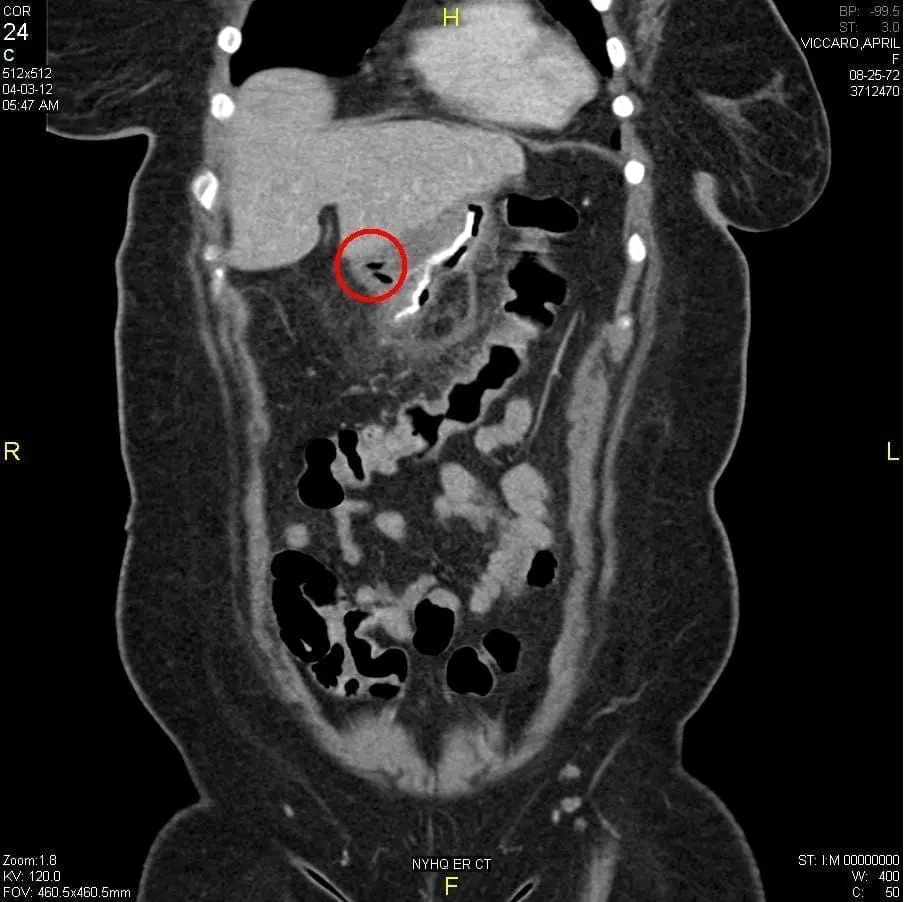

- CT scan

A CT scan is often the first test done when staple line leaks after bariatric surgery are suspected. In the image above next to the red circle you can see a bright white line, which is the staple line. Within the red circle you can see some air bubbles (which appear black). These air bubbles are outside of the staple line, showing that some air that the patient swallowed is now outside of the sleeve.

CT scans are good not only for finding staple line leaks after bariatric surgery, but also for treating them. In some cases the radiologists can insert a small drain tube (called a percutaneous drain) into the area where the leak is, to allow any infection to drain out. This drain is then left in until the leak heals.